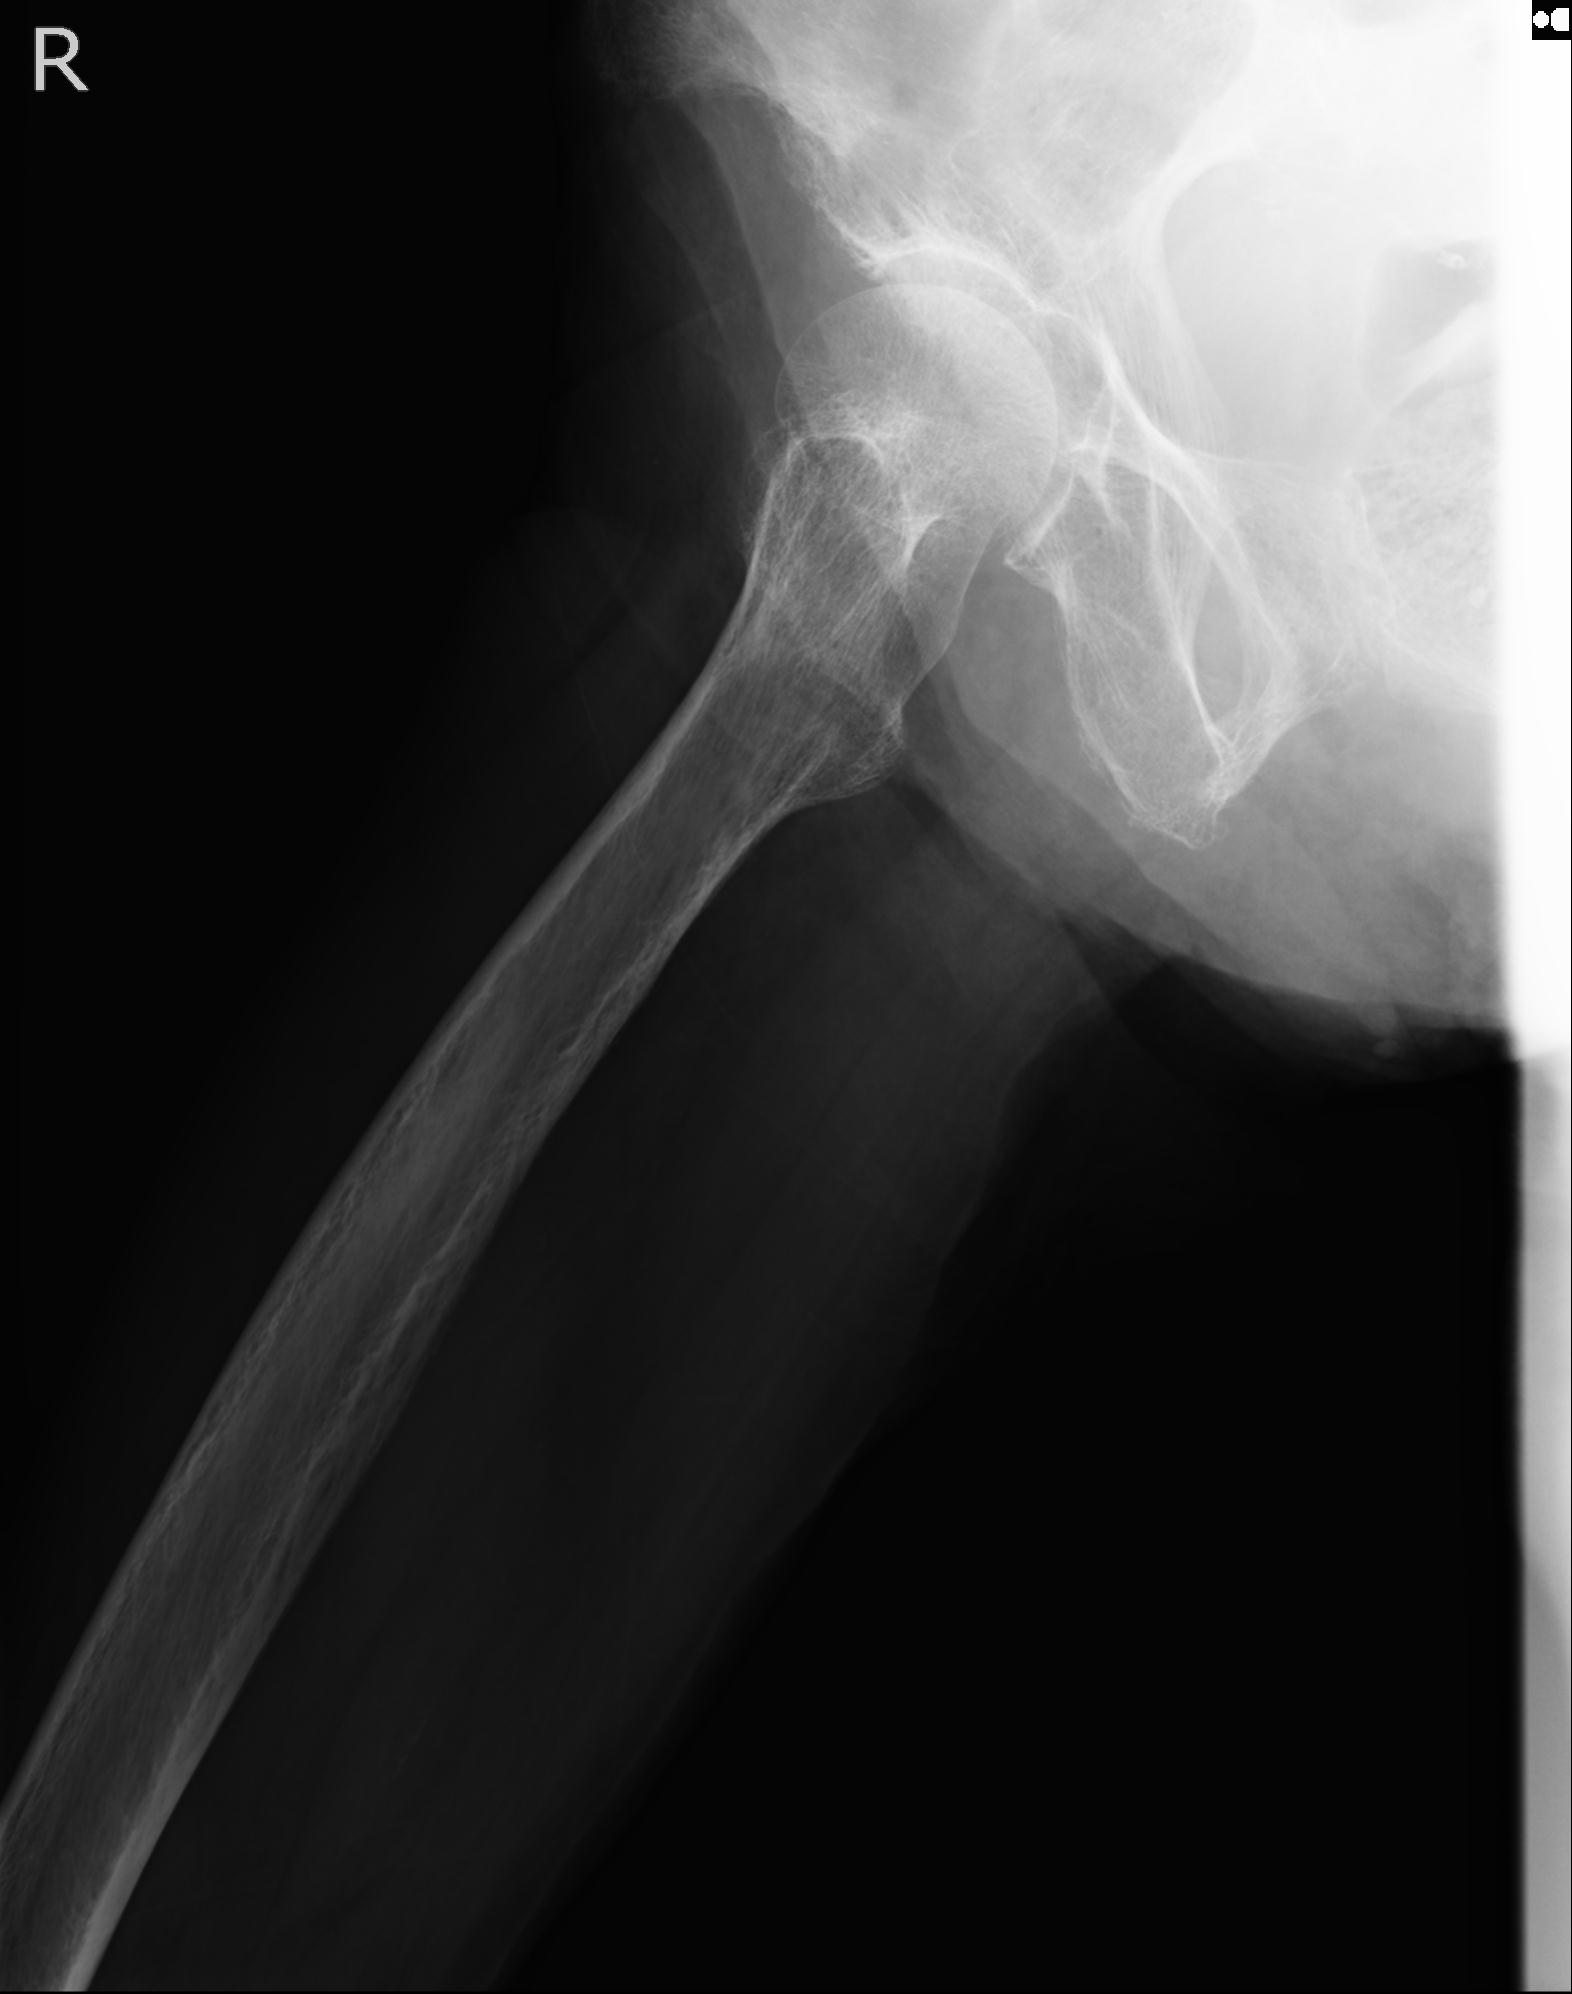

46666 1/28 両股正面+軸と 1/26 右手関節 2R 76歳女性 右転子部骨折